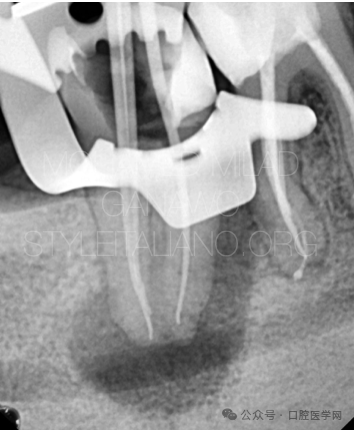

图3

显微镜下可见C形根管的形态走行。